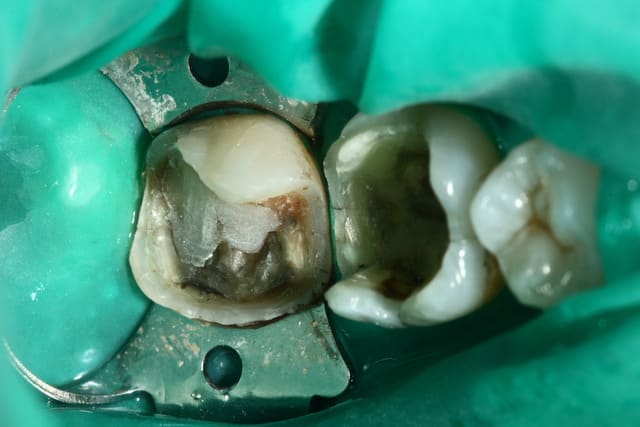

SC12 (35) SC17 (36) sc7 + sc7 (37), 50mn ...

maquillant Enamel HFO

Ben les photos finales c'est après réglage de l'occlusion sinon c'est pas drôle.

Sinon je fais les sillons secondaire a la sonde.

C'est du compo Enamel HRI en dentine et Esthelite en email qui se sculpte facilement et reste pourtant souple et autolissant...

Le polissage c'est des brossettes chargées en silice, et avec de la pâte à polir.